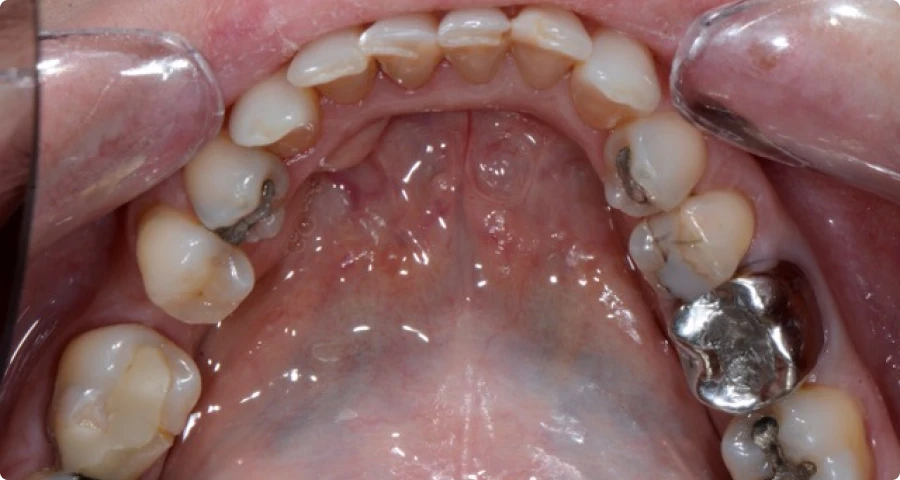

Pour illustrer l’impact de nos traitements, voici quelques exemples concrets de réhabilitations globales réalisées au cabinet Horizon Sourire. Ces cas cliniques montrent différentes situations où des traitements multidisciplinaires ont permis à nos patients de retrouver une santé dentaire optimale. Chaque photo présente l’évolution avant et après les soins, mettant en évidence les résultats fonctionnels et esthétiques obtenus. Ces exemples démontrent notre approche globale, personnalisée et coordonnée, visant à restaurer la mastication, améliorer l’apparence du sourire, et renforcer la confiance de nos patients. Découvrez ces transformations qui témoignent de notre engagement à offrir des soins dentaires de qualité.